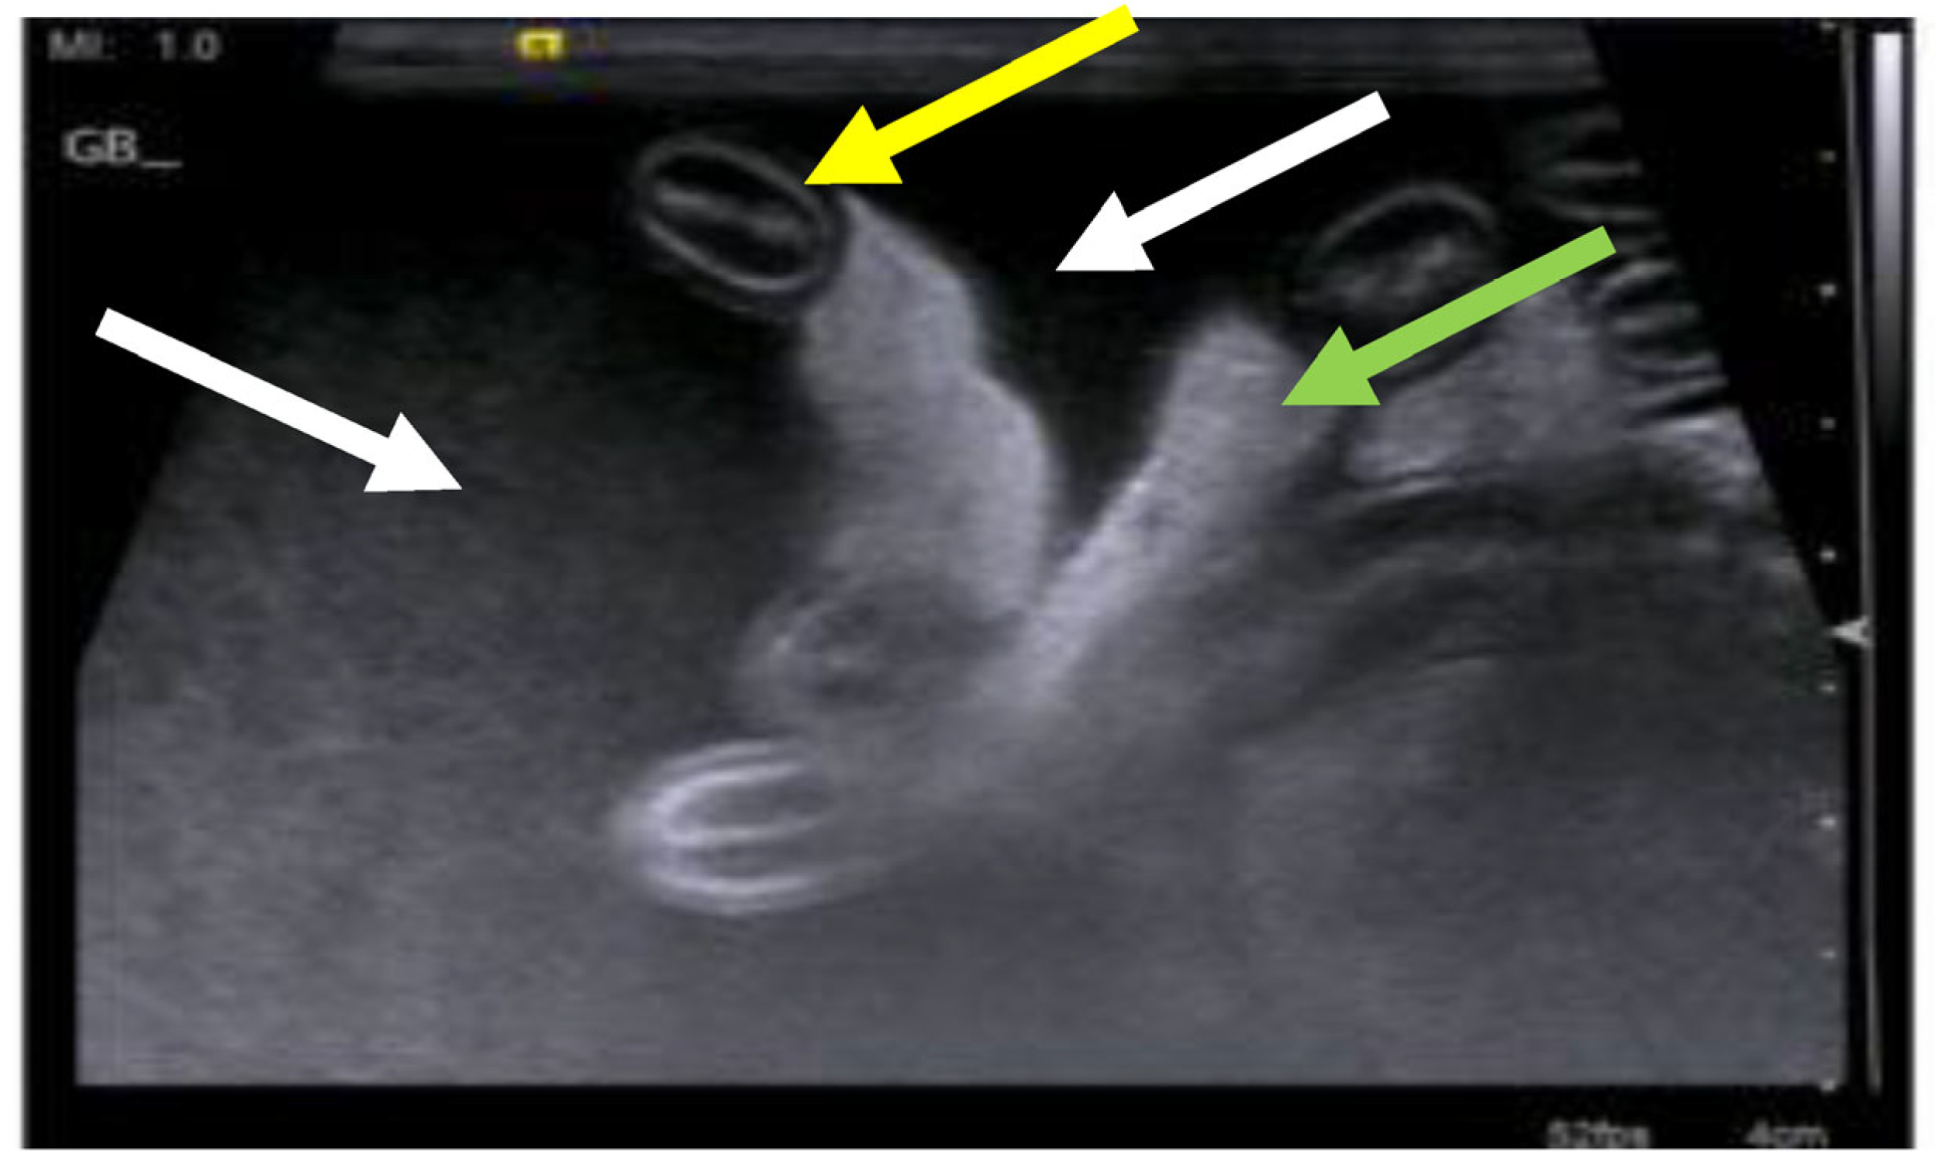

7.2. Approach to the Diagnosis of FIP

| Summary of Section 7: Diagnosis of FIP; Section 7.2: Approach to the Diagnosis of FIP: If an effusion is present, sampling it is the single most useful diagnostic step because tests on effusions have a higher diagnostic value compared to those on blood samples. Samples of effusion can be easy to obtain; imaging (especially ultrasonography) is used to confirm, identify, localise, and sample smaller volumes. FIP effusions are usually clear, viscous/sticky and straw-yellow in colour. Diagnosing FIP if there is no effusion present is more challenging due to the large number of possible clinical signs and their non-specific nature (e.g., anorexia, lethargy, weight loss, fever) and because biopsy collection ante-mortem can be very difficult due to, for example, problems accessing affected tissues, contra-indications for general anaesthesia or invasive biopsy collection in a sick cat, and/or costs involved in tissue collection. Cases with neurological or ocular signs can be approached via the sampling of cerebrospinal fluid or aqueous humour, but these techniques are not performed commonly outside of referral clinics. There is no non-invasive, confirmatory test available for cats with FIP that do not have effusions, although in some cases valuable supportive information can be gained through the analysis of fine-needle aspirate (FNA) samples collected from affected organs, if accessible. Tissue FNAs are usually easier to collect than tissue biopsies. The integration of multiple test results is most useful to help direct the clinician to a diagnosis of FIP being very likely, in the absence of confirmatory testing. |

7.4. Diagnostic Imaging in FIP

7.4.1. Routine Imaging: Ultrasonographic and Radiographic Findings

| Summary of Section 7: Diagnosis of FIP; Section 7.4: Diagnostic imaging in FIP: No specific ultrasonographic or radiographic findings exist for FIP. Ultrasonography (in particular) and radiography can show the presence of effusions. Pneumonia due to FIP that is occasionally reported can be associated with radiographic changes. Ultrasonography can reveal abdominal lymphadenomegaly or lymphadenopathy and/or abnormalities of the liver, spleen, intestines and/or kidneys (which can include a medullary rim sign), depending on which organs are affected. Imaging can also be of use to the direct sampling of abnormal tissues, e.g., fine-needle aspirate for cytology examination to reveal non-septic pyogranulomatous inflammation, or ultrasound-guided needle core (e.g., tru-cut) biopsies can be collected and submitted for histopathology. When a cat is showing neurological signs, the imaging of the brain by magnetic resonance imaging, if available, with contrast, can be useful to demonstrate neurological abnormalities (such as obstructive hydrocephalus, syringomyelia, foramen magnum herniation and marked contrast enhancement of the meninges, third ventricle, mesencephalic aqueduct, and brainstem). A description of computerised tomography findings in cats with neurological FIP has not been published, but MRI is likely to be more sensitive in the detection of subtle intraparenchymal lesions. Advanced imaging of the central nervous system is indicated before performing cerebrospinal fluid sampling to assess the potential risk of herniation. |